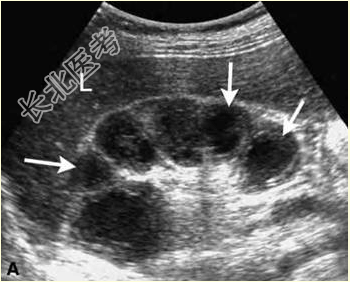

- [材料题] 患者女,40岁,因“尿频、尿急、尿痛及血尿3个月”来诊。尿常规:大量白细胞和少量红细胞。声像图表现见下图。

- 简答题1、其超声诊断包括哪些?

- 简答题2、为明确诊断,需要进一步检查什么?

- 简答题3、如不及时治疗,该病还可能累及哪些部位?

- 简答题4、该病在体内的播散的方式有哪些?